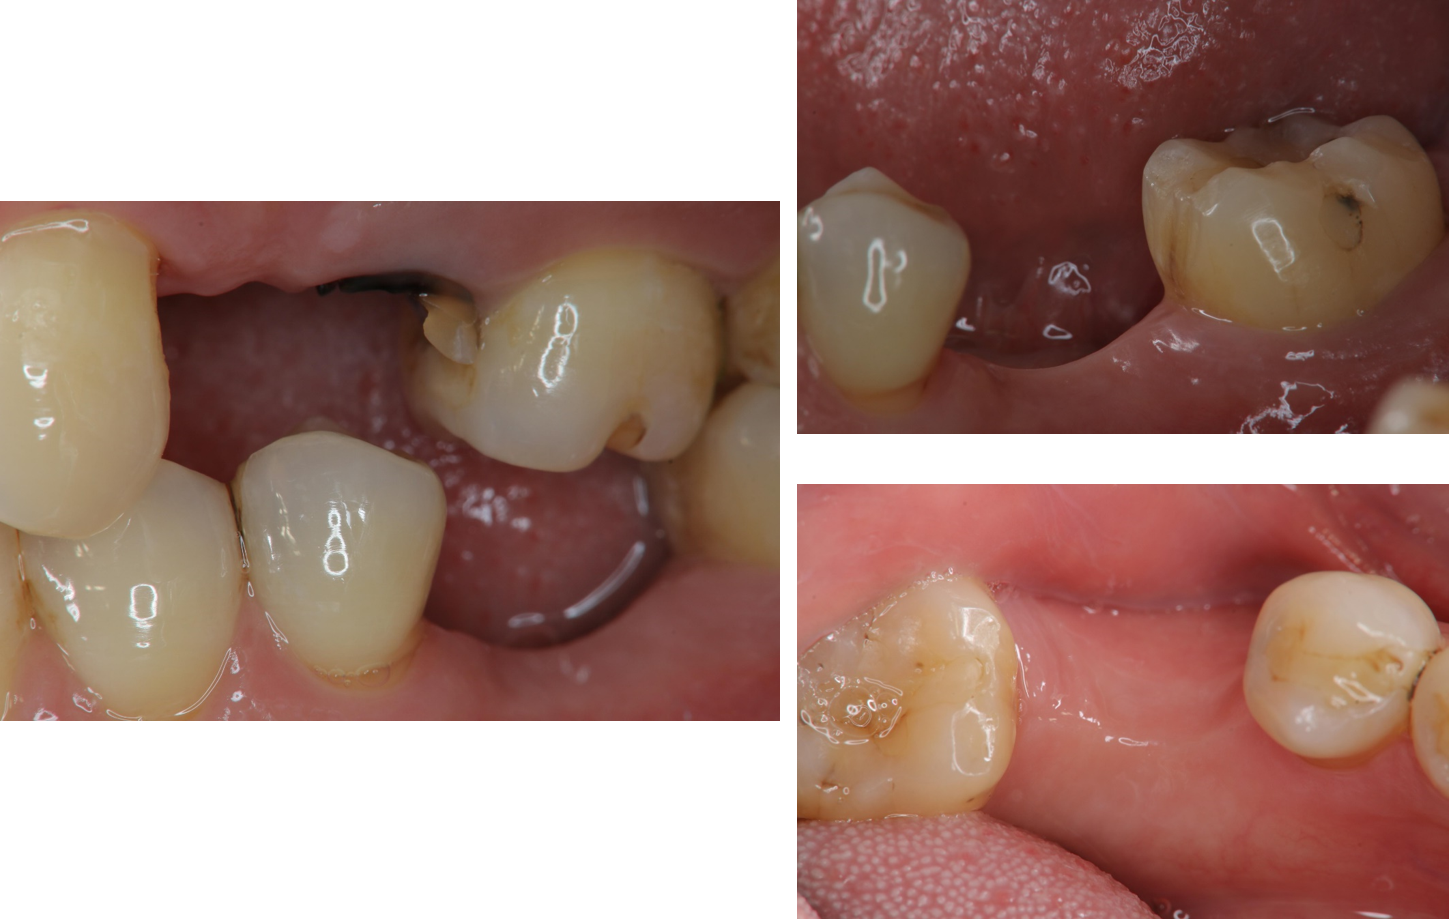

治療後,上顎植牙口內適應良好

治療後,下顎植牙口內適應良好

術前、術後比較